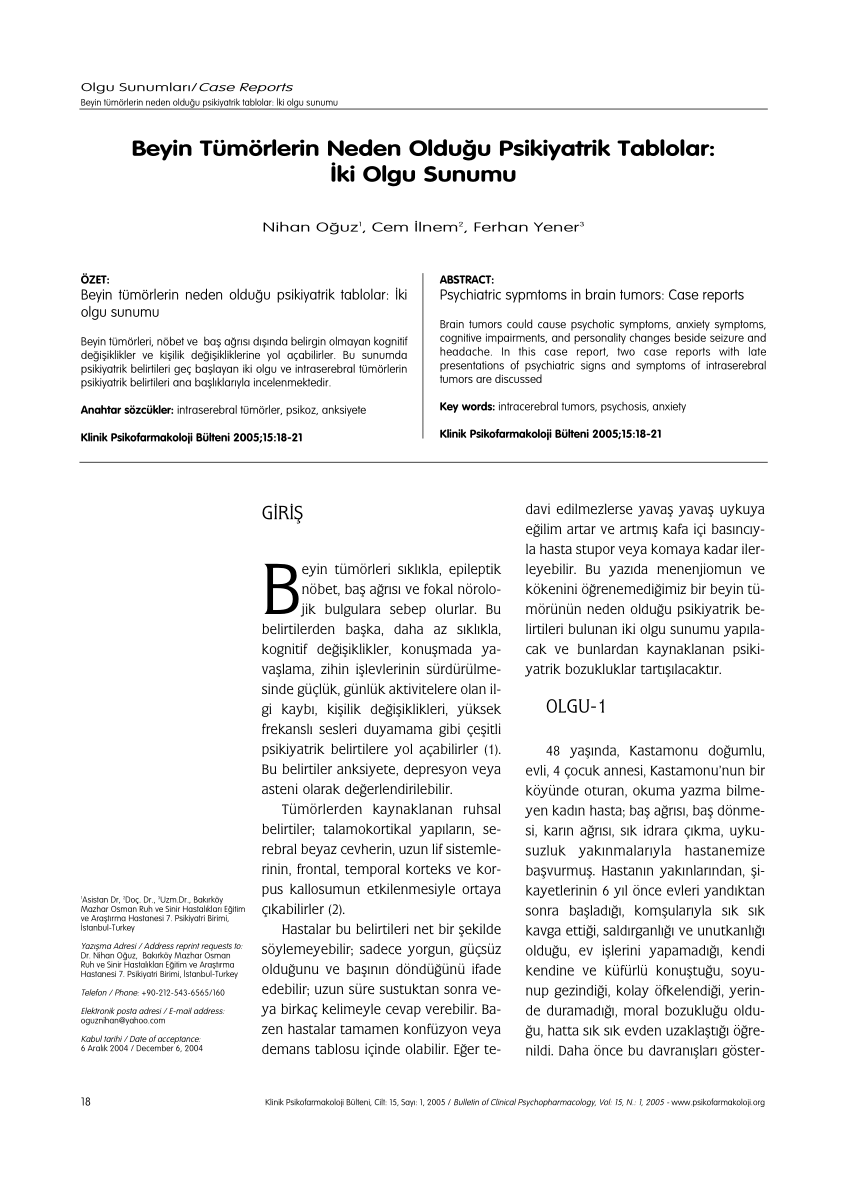

Beyin tümörü uyku hali. Yetişkinlerde ikincil beyin tümörleri birincil beyin tümörlerinden çok daha yaygındır. Ancak şikayetler çok daha çeşitlilik gösterebilir. 1925 yılından beri bilinen bu beyincik tümörü çok ayrı hücresel ve klinik özellikeri olan ve oldukça habis karekterli bir beyincik tümör tipidir beyinciğin çocuklarda en sık tümörü olup tüm primer beyin tümörlerininin 4 10 teşkil ederler. Patoloji alındı ondada tam teşhis konulmadı.

Gün içinde halsizlik ve sürekli uyku hali sabahları ise baş ağrısı ve ağız kuruluğu ile uyanmalar tipiktir. Uyku tüm tümörlerin ortak belirtisi değildir fakat bazılarında görülür. Beyin tümörü hastalarının son günleri nasıl anlaşılır. şimdi radyoterapi ve kemoterapi alıyor.

Uykuyu kontrol eden sinirler beyin sisteminde yer aldığı için sürekli uyku problemini çözmek için nöroloji bölümüne gitmeniz gereklidir. İkincil beyin tümörleri en sık kanser öyküsü olan kişilerde görülür. Denge kaybı uyku hali gözde görme sorunları duyma sorunları el ya da ayaklarda his sorunları ruhsal değişiklikler halüsinasyonlar görebilir yemek yeme sorunları yutkunma sorunları yemek yeme sorunları halsizlik trombosit düşüklüğü lökosit. Sadece uyku hali be yorgunluğu vardı.

Sonrasında bulantı kusma şuur dalgalanmaları uyku hali baş dönmesi ve nöbet geçirme vücudun farklı bölgelerinde kuvvetsizlikler iştahsızlık unutkanlık gelmektedir. Bunların en başında yeterince uyumamaktır. Ancak çocukluk yaşı tümörlerin 15 20 sini teşkil etmektedir. Beyin tümörü uyku yapar mı.

Nöbet geçirmesi şimdiye kadar olmadı. Uyku apnesi bulunanların kalp damar hastalıklarına ve beyin damar hastalıklarına inme gibi yakalanma riski daha yüksektir. Ancak baş ağrısı bazen beyin tümörü beyin kanaması ve anevrizma gibi yaşamı tehdit eden. Ancak nadir durumlarda metastatik beyin tümörü vücudunuzun başka yerlerinde başlayan kanserin ilk belirtisi olabilir.